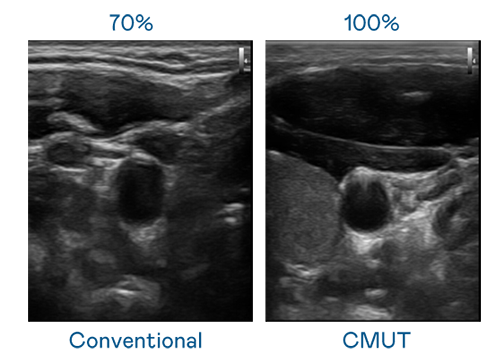

CMUT 技术是一种用电容式微机电元件来产生超音波讯号的技术。与传统 PZT 压电式技术相比,CMUT 频宽增加 30%,更宽频的超音波讯号让影像解析度大幅提升,是实现高影像品质医疗超音波扫描、促进精准医疗发展的关键技术。

超音波影像的解析度高低,首先取决于探头能发出的讯号频宽。U8国际 CMUT 可提供高清晰的超音波讯号,提供高频宽、高灵敏度、影像纹理细节更高的超音波影像,协助医护人员缩短影像判读时间及利用精准的医疗影像进行诊断。